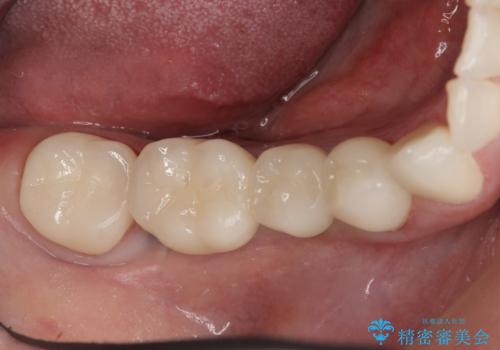

- 右下でものを咬むと痛むので診て欲しいといらっしゃった方の症例です。

右下6番目の歯を診査したところ歯根が破折していたため、保存不可能であることを説明し抜歯しました。

その後右下5、6番目にはインプラントを埋入し、右下3、4、5、6、7番の歯の補綴をオールセラミッククラウンによって行いました。

今回用いたオールセラミッククラウンはジルコニアフレームという白い素材の上にセラミックを盛っているため、審美性が非常に高いのが特徴です。

また、ジルコニアは人工ダイヤモンドの材料にも使われているほど高い強度を持っており、そのためオールセラミッククラウンは審美性だけでなく、奥歯やブリッジの補綴も可能とするクラウンです。